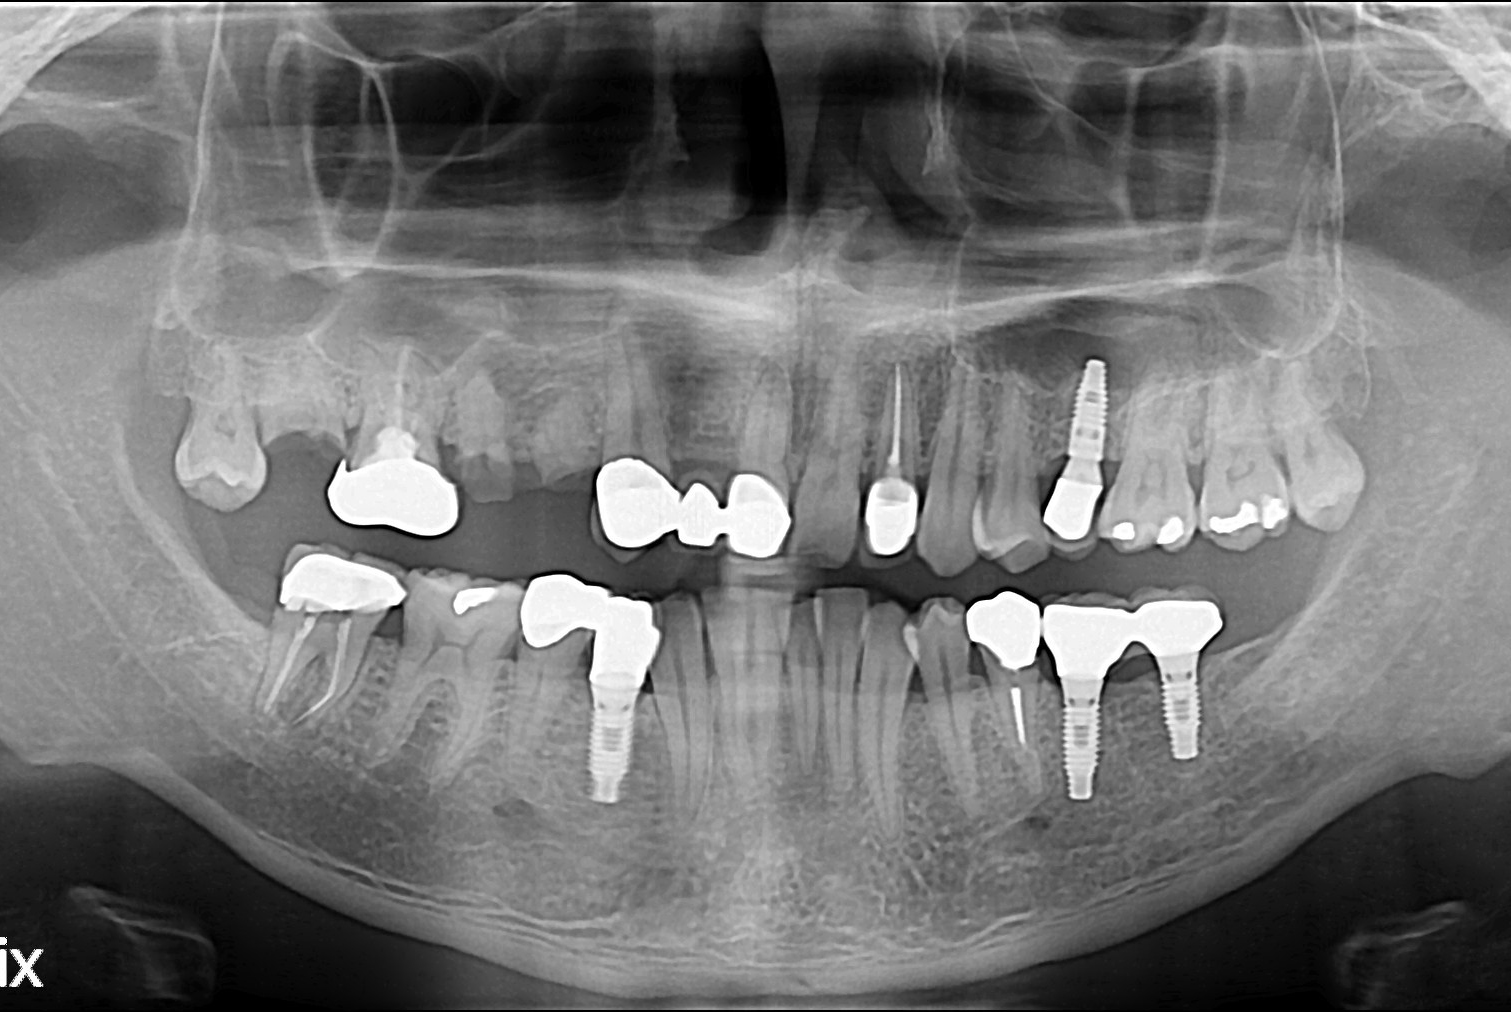

[임플란트] 임플란트

치료전 : 2017-04-20

세종치과는 많은 환자와 다양한 케이스를 바탕으로 항상 편안한 임플란트 수술을 제공하고자 노력하고,

오래동안 튼튼히 쓸 수 있는 임플란트 수술을 가장 큰 목표로 삼고 있습니다